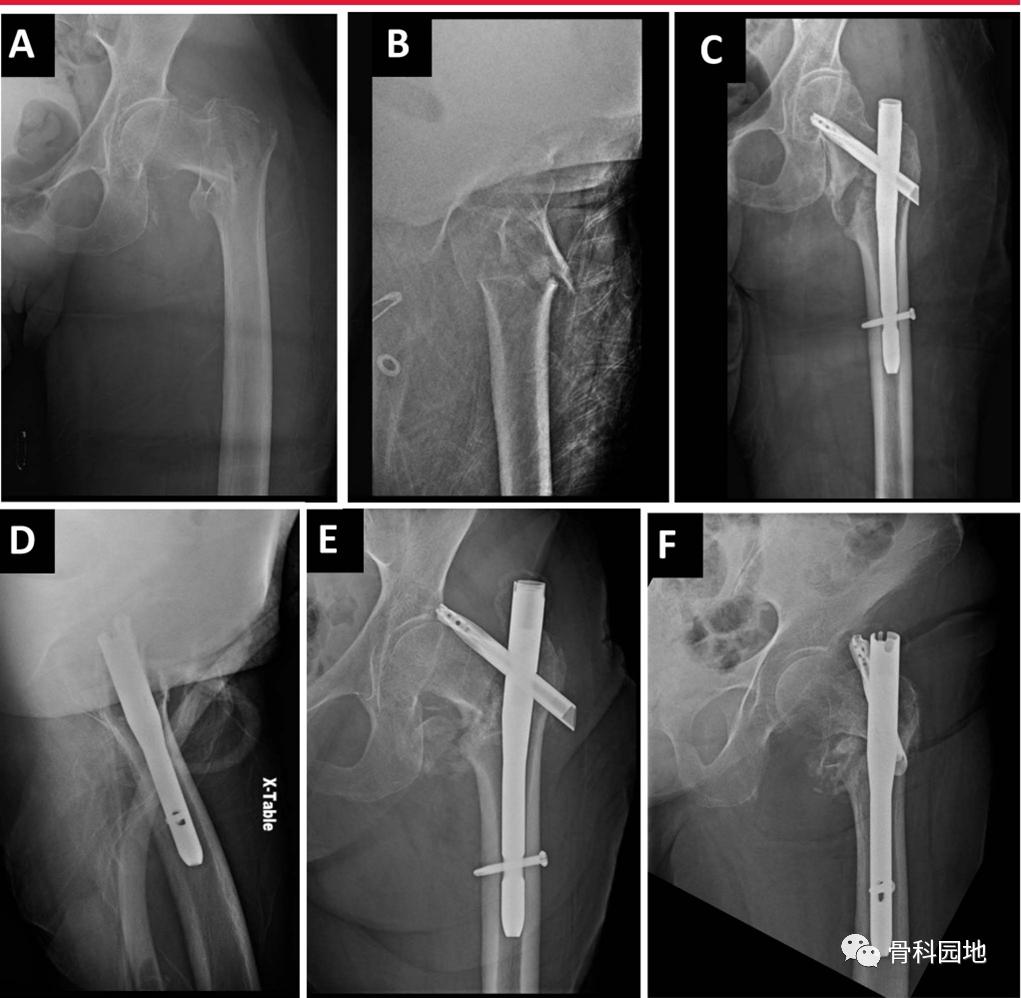

最佳的内固定位置对于维持骨折复位和降低内固定失败的风险至关重要。特别是开口,可以显著影响整个冠状面和矢状面对齐骨折粗隆髓内装置治疗转子周围骨折可使植入物复位不良。

首选的方法是使植入物长轴与股骨轴线对齐,以避免内翻复位不良,内翻复位不良通常位于转子尖端内侧。为了在矢状面与股骨管对齐,起始点应该在转子顶点后约5毫米处,以允许其前偏移。对于转子下骨折,尤其重要的是矢状面开始位置不要太前。生物力学和临床研究普遍认为,螺钉或螺旋刀片的适当位置应位于侧位正中,AP位正中或下位。

A, x线片显示74岁女性,表现为左侧髋关节转子间骨折。B,侧位图像显示股骨粗隆间粉碎性骨折。C,术后AP图像显示外翻复位和不适当的尖-尖距离。D,术后侧位图像显示较大的端-端距离。E,术后6周AP图像显示内翻塌陷,螺旋刀片切开。F,术后6周的侧位图像显示螺旋刀片切口。